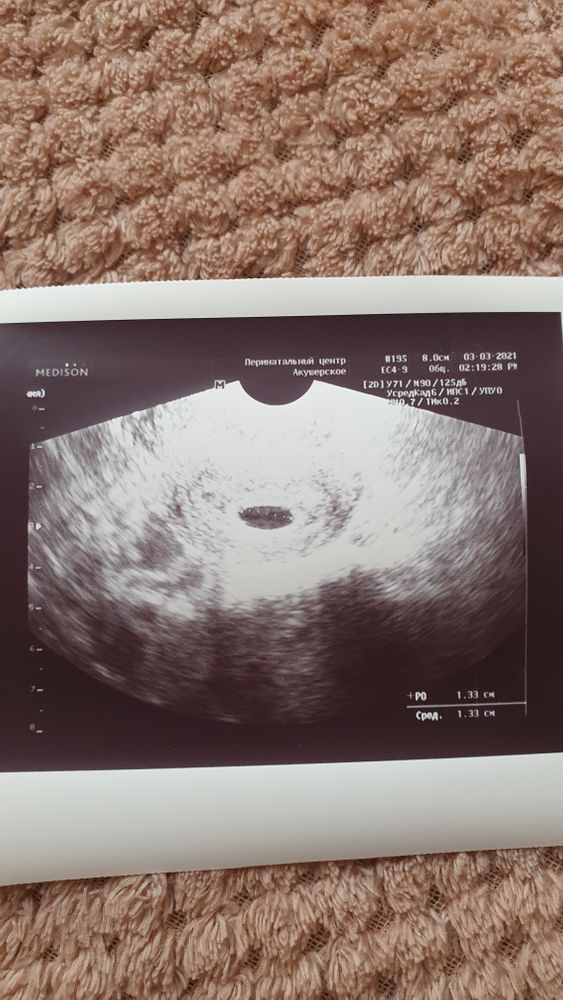

20дпп УЗИ

Всё о нашей беременностиА вот и первое фото малыша 🥰 ещё совсем кроха, посмотрели только местоположение, все хорошо находится в матке, желточный мешочек есть, сердечко пойдём слушать 12.03. 🤗